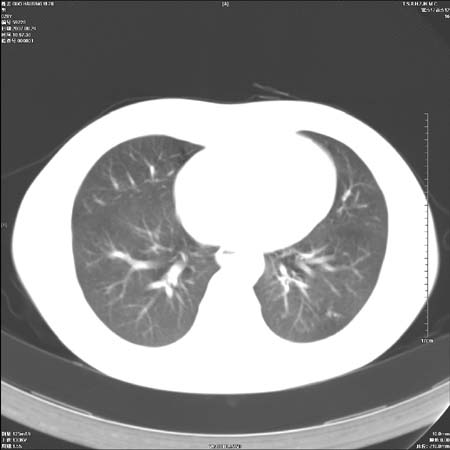

男性,28岁,体检发现左肺病变,患者只有背部隐痛感,哀哉,真不忍心下诊断啊。

左肺门区软组织肿块,左肺上叶支气管开口消失,纵隔内见肿大淋巴结,考虑左中心型肺部,可以做纤支镜取病理确认.

左肺门区分叶状软组织肿块,纵隔内有肿大淋巴结,诊断肺癌应该问题不大。

直接下肺癌诊断还太早,病灶较大,估计5cm以上,但阻塞性改变及对临近纵隔及支气管侵犯不明显,密度较均匀,弓旁见一单个淋巴结,需要排除炎症性肿块及腺瘤,平滑肌瘤等。